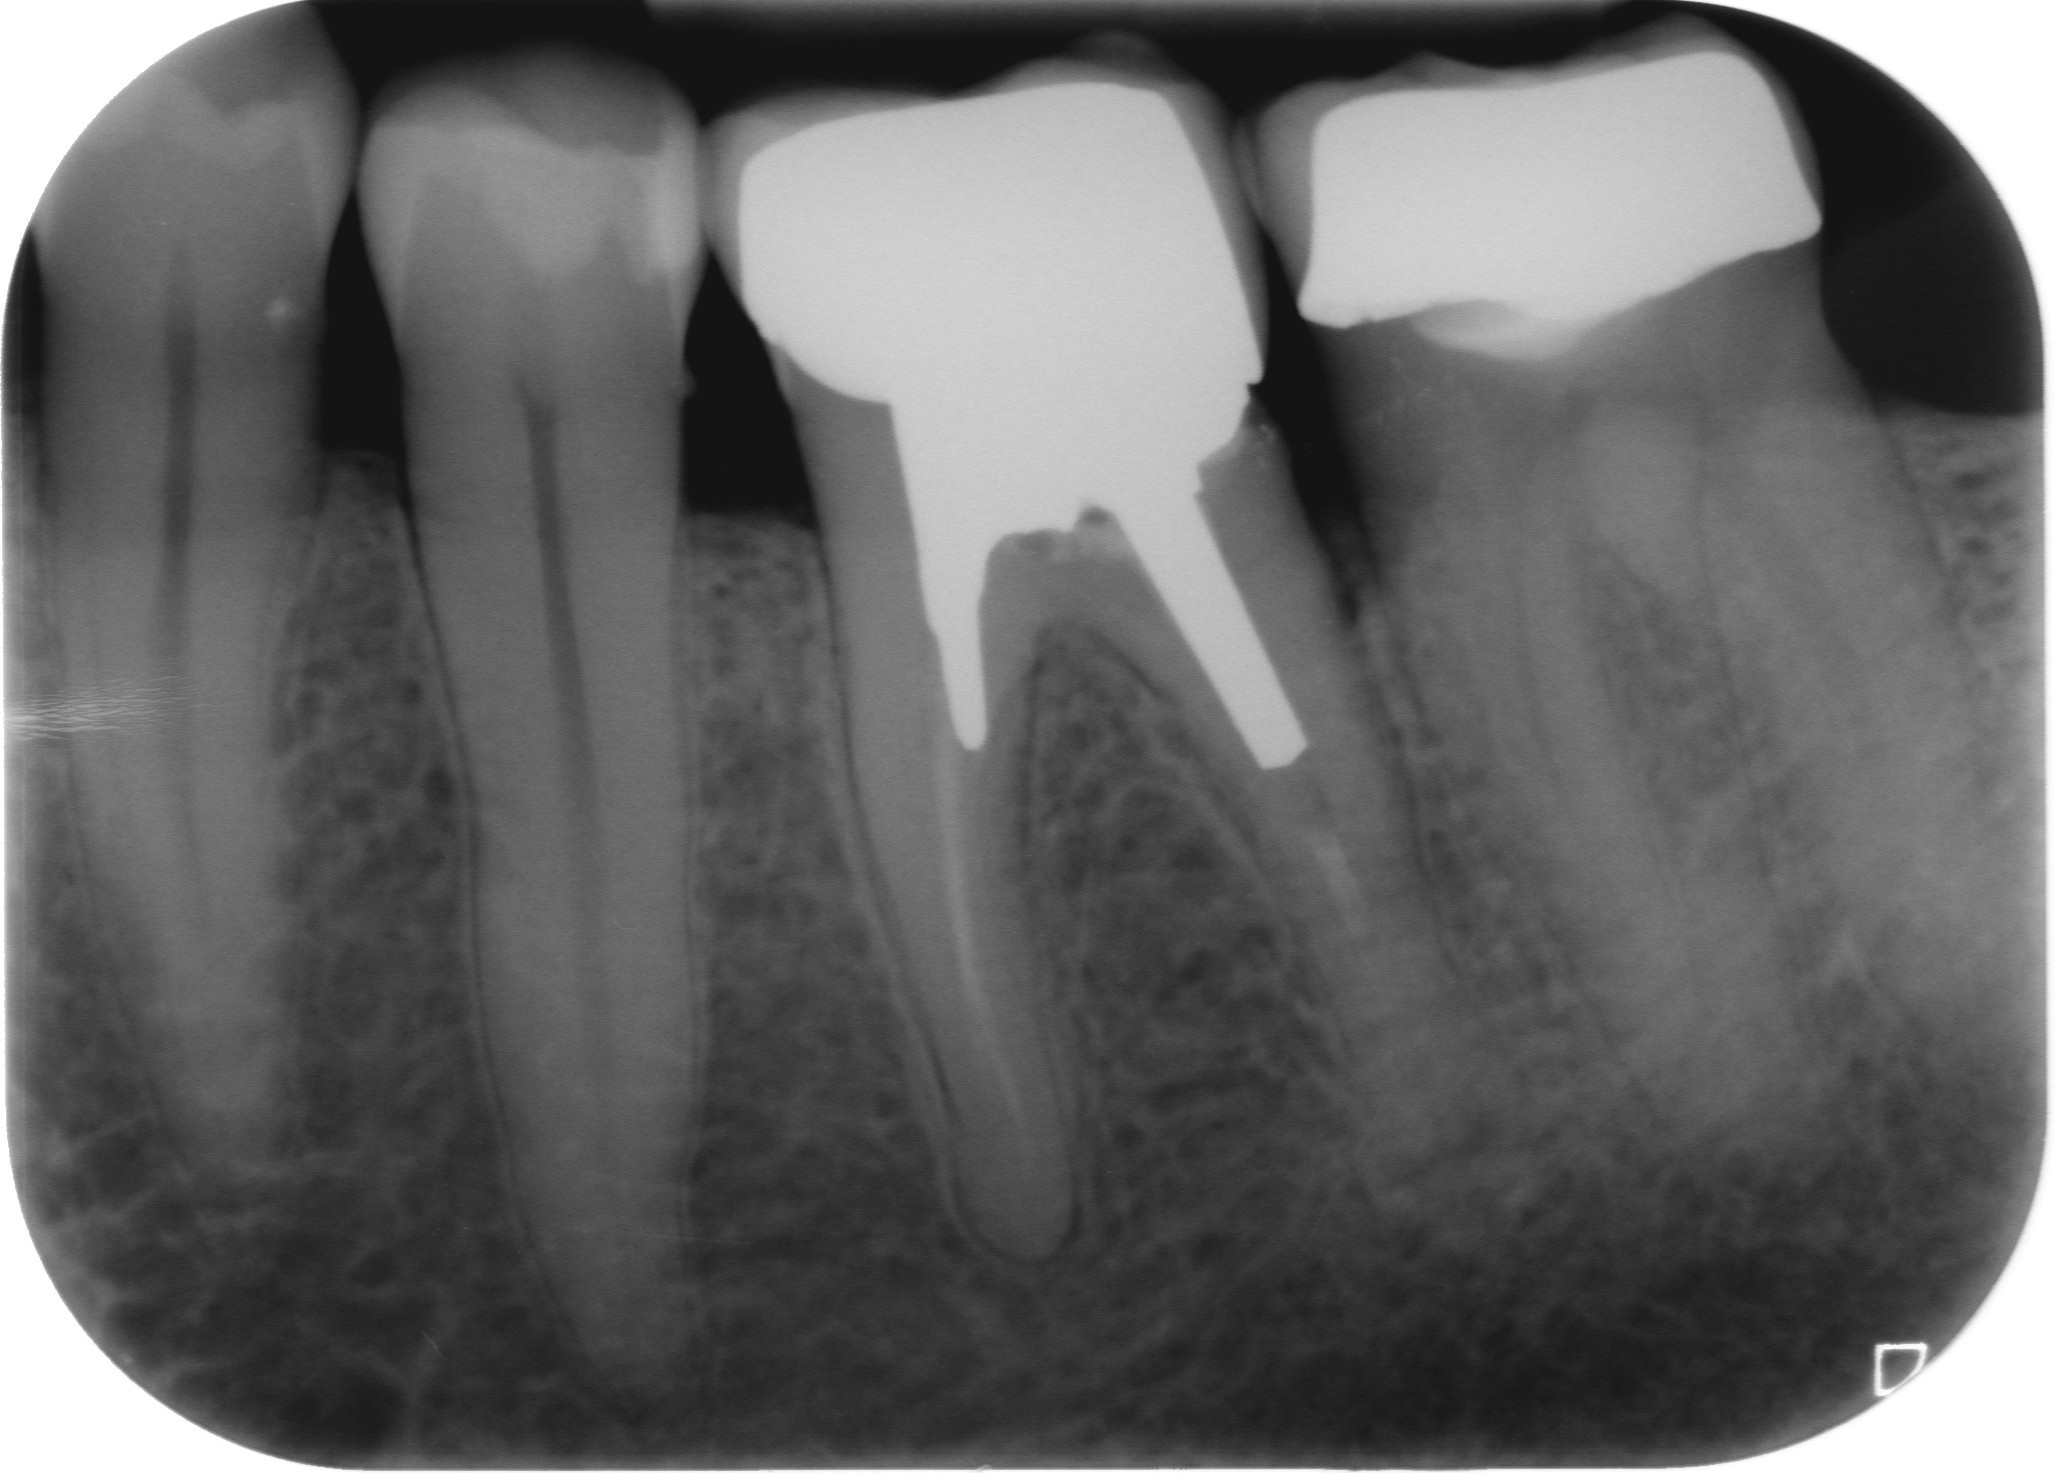

Fig. 1 : Radiographie préopératoire montrant la présence d’une reconstitution corono-radiculaire coulée, ancrée dans les trois canaux.

D’un point de vue pratique, la première étape consiste à réduire les dimensions du tenon s’il occupe une grande partie de la structure coronaire, de préférence en lui donnant une forme cylindrique similaire à celle d’un tenon préfabriqué. De même, une reconstitution corono-radiculaire coulée ancrée dans plusieurs canaux doit d’abord être sectionnée jusqu’au niveau du plancher de la cavité pulpaire, afin de la traiter comme un ensemble de tenons unitaires, ce qui diminue le degré de rétention global du système. La réduction du tenon doit être effectuée avec des fraises en carbure spécialement conçues pour découper le métal, sous une irrigation abondante. Les évaluations cliniques et radiographies préliminaires sont essentielles pour planifier l’angle de coupe. La procédure doit être fréquemment vérifiée et, si nécessaire, il convient d’effectuer des contrôles radiographiques avant qu’une quantité excessive de dentine ne soit sacrifiée (Figs. 1–3).